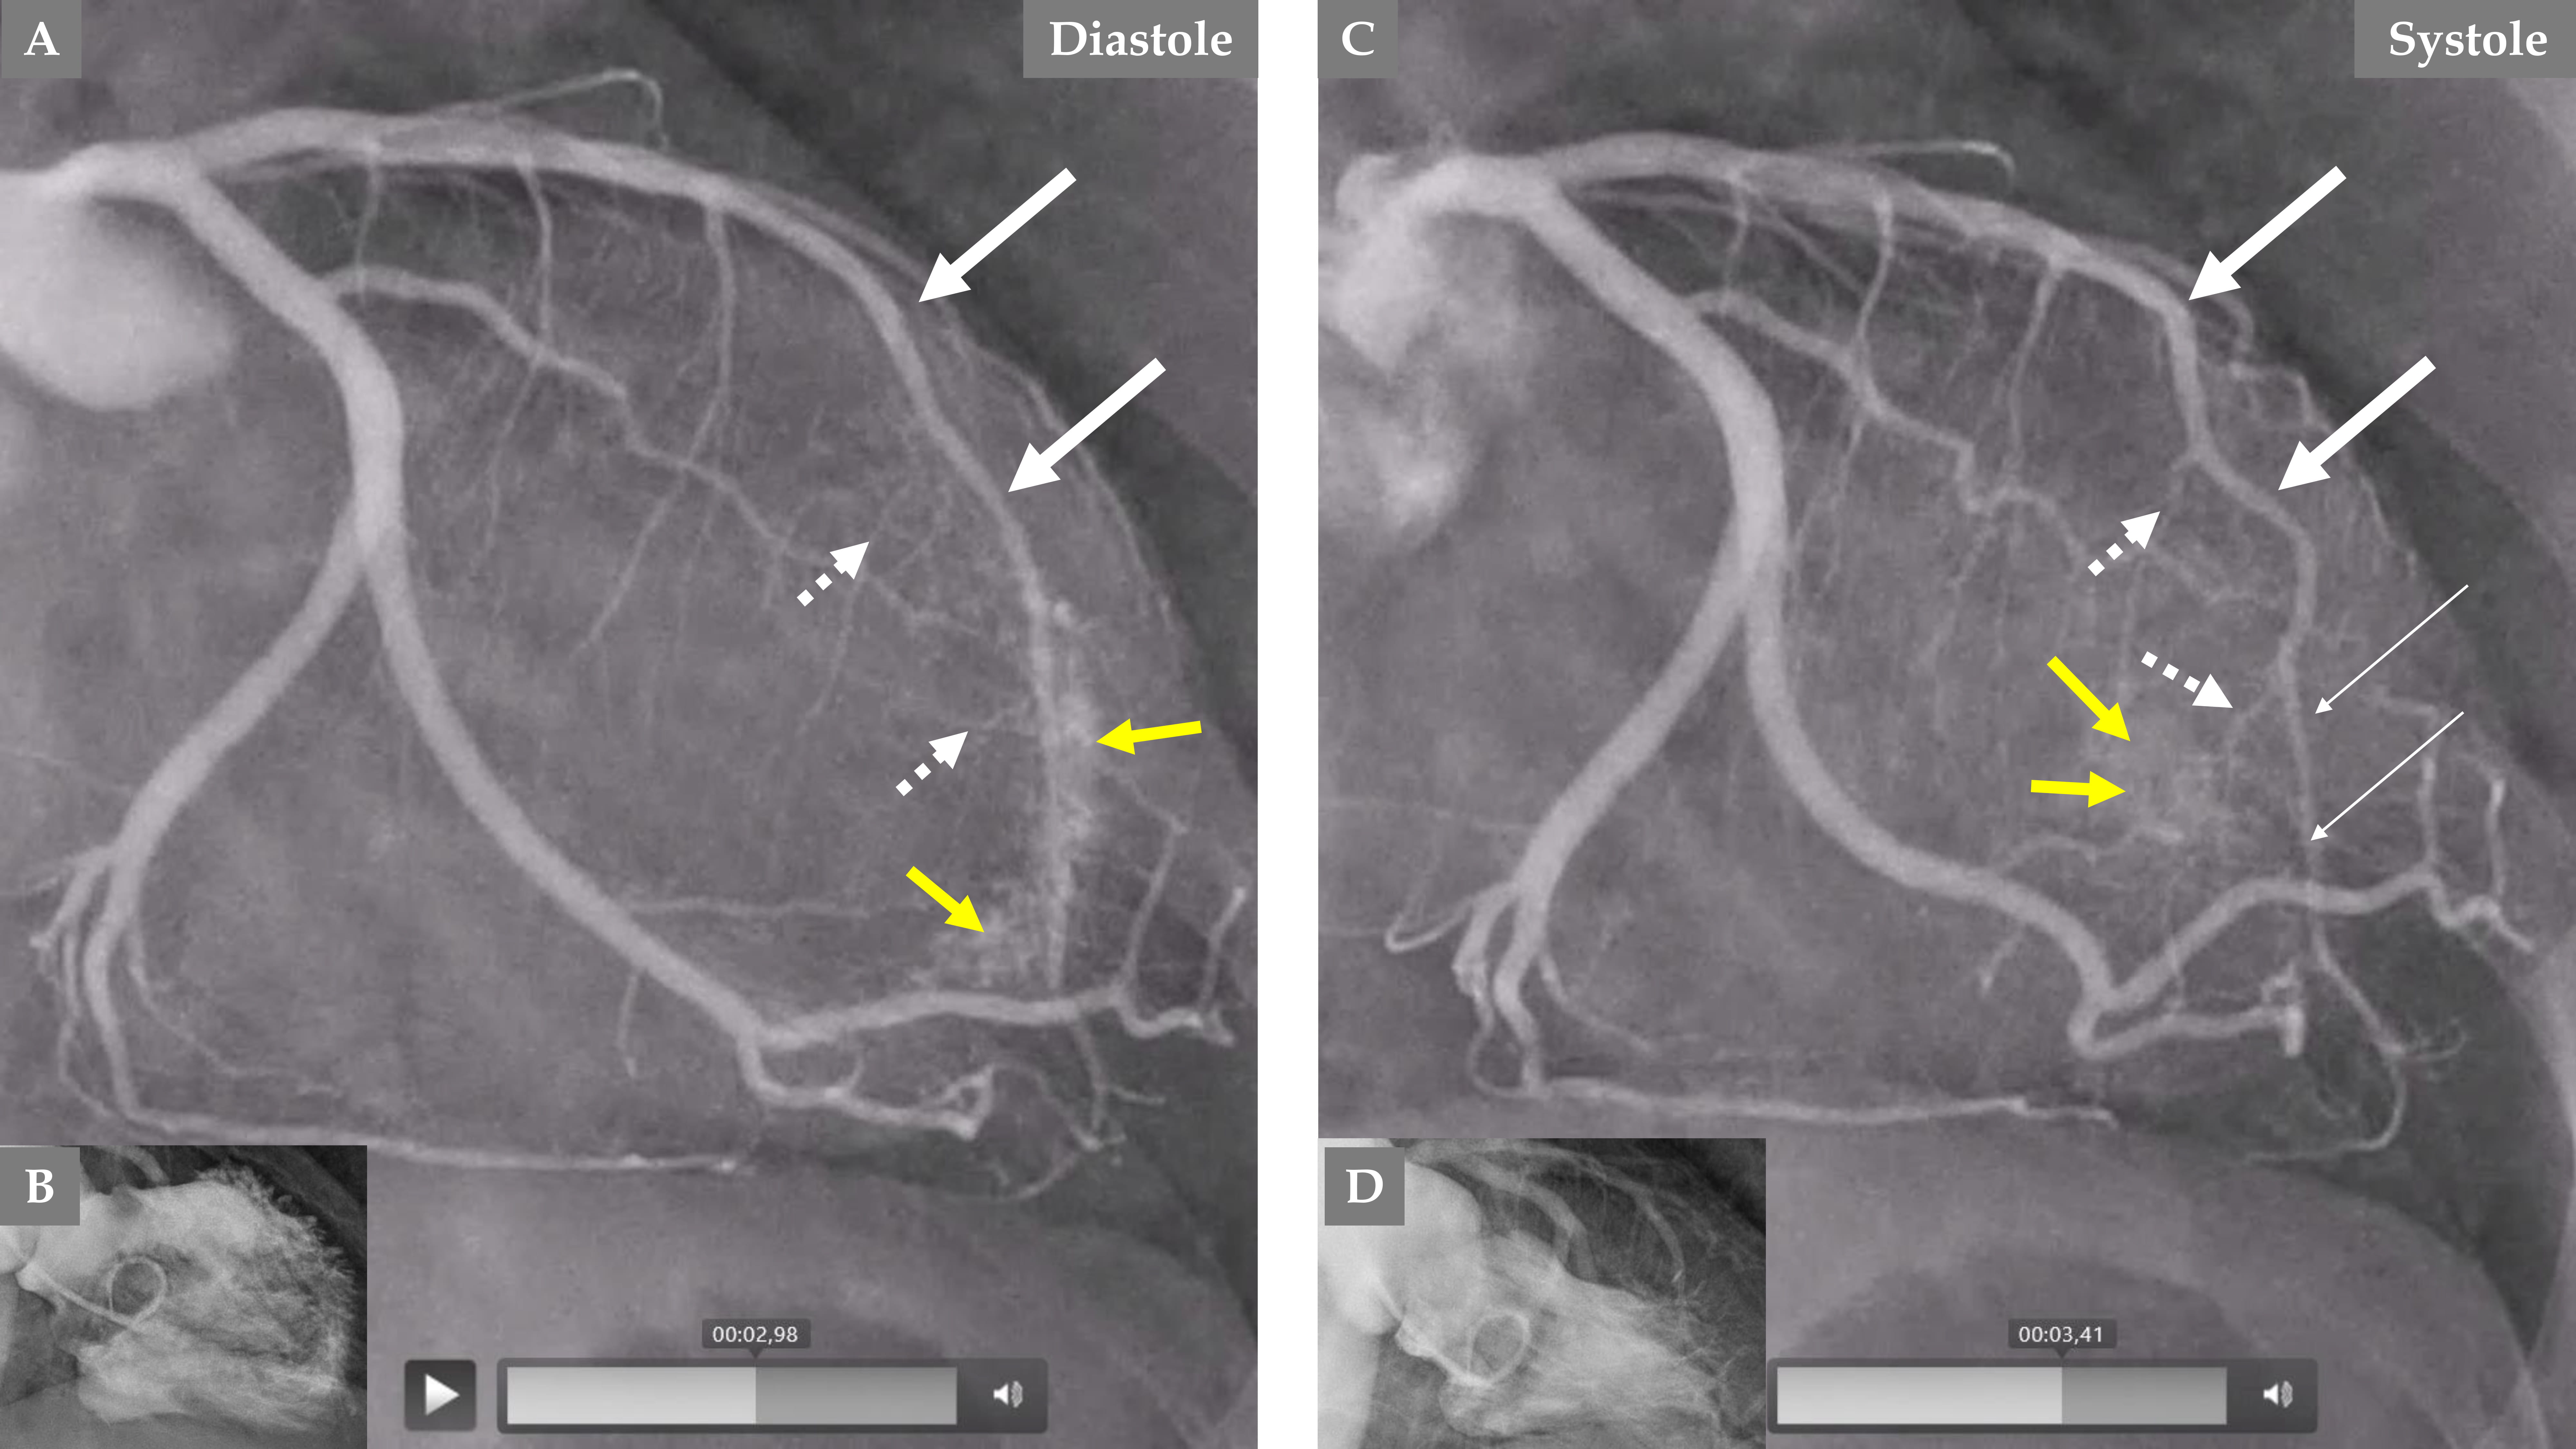

Fig. 4. Demonstration of remarkable changes in the LCA 5 months after the index presentation when the left ventricular dysfunction is completely normalized. LCA angiography during diastole (A). Contrast left ventriculography during diastole (B). LCA angiography during systole (C). Contrast left ventriculography during systole (D), which shows complete normalization of the left ventricular function. The LAD has a normal diameter, especially in the proximal two-thirds (A and C, thick white arrows), but mild systolic compression in the distal segment (C, thin white arrows). The septal branches from the distal half of the LAD are seen now during both diastole and systole (A and C, broken white arrows). The most remarkable change is the emergence of contrast in the left ventricle (yellow arrows during diastole in A and systole in C) due to reopening of the coronary artery–left ventricular micro-fistulae draining into the left ventricle.

During the follow-up 5 months later and with normalization of the LVWMA, all the above-mentioned changes in the septal branches, the LAD changes, and flow were normalized. Mild distal systolic LAD compression is seen most likely due to myocardial bridging (Fig. 4C).

An interesting finding, which forms a novel observation, is that no signs of CALVMF was observed during the index presentation with a mid-apical ballooning pattern of TS (Fig. 3C and Fig. 5A); however, during follow-up coronary angiography when the left ventricular dysfunction has completely normalized, there was clear signs of CALVMF, most probably arising from the distal marginal branches (Fig. 4A,C during diastole and systole and Fig. 5C). It is also clearly seen that the contrast staining moves to the left ventricular cavity during systole (Fig. 4C). These micro-fistulae were not visible during index presentation because of the compression by the myocardial stunning (myocardial cramp) caused by TS. The comparison between the index presentation, where there were no signs of CALVMF, and the follow-up 5 months later, where signs of CALVMF appeared clearly, is demonstrated in Fig. 5.